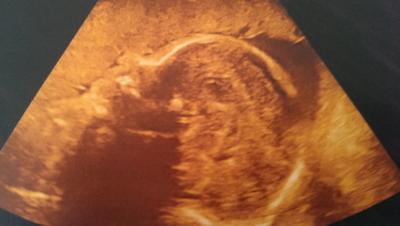

Hi, letzte Woche war ich nochmal zur Feindiagnostik und habe ein Bild von der Maus bekommen. Die Nase sieht so merkwürdig aus und jetzt bin ich die ganze Zeit am grübeln ob meine kleine so auf die Welt kommt oder ob es nur so merkwürdig aussieht da sie ihren Kopf in die plazenta drückt. was meint ihr dazu?

Bild zu verunsichert wegen us-Bild - Forum für Januar - Mamis